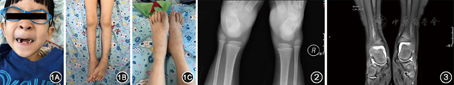

体格检查:身高94 cm,体重18.5 kg。神志清,反应可,体形消瘦,面色苍白,全身无皮疹;颈部、颌下及锁骨上可扪及肿大淋巴结,最大2 cm×1.5 cm,质软光滑,无触痛,活动度欠佳,局部无红肿;口唇干燥、苍白,可见龋齿,呼吸稍促,双肺呼吸音粗,未及干湿性啰音;心音有力,律齐,未闻及病理性杂音;腹部膨隆,肝肋下4 cm,质韧光滑,脾脏右肋下平髂前下棘。双膝、双踝、右腕关节肿胀伴活动受限(图1),局部皮温升高,触痛明显,四肢肌力及肌张力正常,神经系统查体未见异常。毛细血管充盈时间1 s。

影像学检查:腹部超声提示肝脾弥漫性增大(肝右肋下3 cm、脾左肋下4 cm),肠系膜多增大淋巴结;关节超声提示双肘、双膝、双踝、双腕关节滑膜囊积液伴滑膜增厚;踝关节正侧位X线片提示双踝关节软组织肿胀,关节面光滑,关节对位良好(图2);踝关节磁共振成像(MRI)提示双踝关节积液,滑膜明显增厚伴强化(图3)。心电图、脑电图、心脏超声、胸腹CT、头颅MRI均未见明显异常。